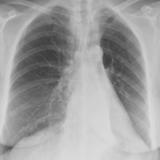

Gallery Lobar Collapse

Lobar Collapse

LUL Collapse

Album: LUL Collapse

LLL Collapse

Album: LLL Collapse

RLL Collapse

Album: RLL Collapse

RUL Collapse

Album: RUL Collapse

RML Collapse

Album: RML Collapse